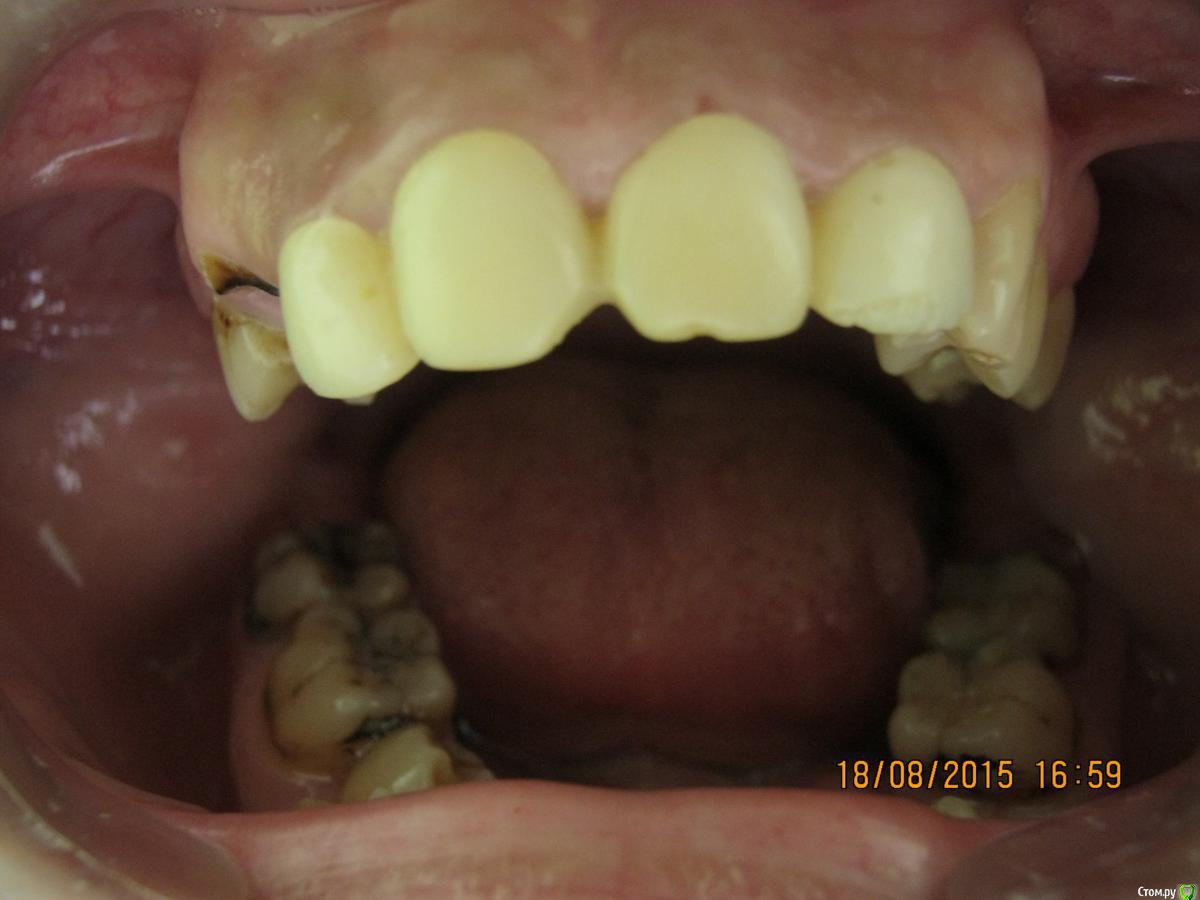

SeregaStomatolog Опубликовано 18 августа, 2015 Поделиться Опубликовано 18 августа, 2015 Добрый вечер уважаемые коллеги!В клинику обратилась пациентка с такой ситуацией во рту.Подскажите пожалуйста что можно сделать и с чего начать. Ссылка на комментарий

SeregaStomatolog Опубликовано 18 августа, 2015 Автор Поделиться Опубликовано 18 августа, 2015 Во-первых она хочет нормально улыбаться,не стесняясь отсутствующего клыка.Во-вторых она хочет нормально жевать,т.к. отсутствие 1.7,1.6 не позволяет это делать.Я сразу сказал пациентке что вариантов без ортодонтии мало (если они вообще есть) и обещать ничего не стал.Случай сложный,поэтому хочется узнать в принципе,на будущее,какие варианты лечения возможны (если можно по подробнее).Пока что я снял слепки,отлил модели-пошел за советом к коллегам в другую клинику-все настаивают на ортодонтии.Теперь вся надежда на Вас коллеги,подскажите что можно придумать более менее приемлемое без ортодонтии. Ссылка на комментарий

SeregaStomatolog Опубликовано 18 августа, 2015 Автор Поделиться Опубликовано 18 августа, 2015 Сделав как хочет пациентка вы не получите красивый результат, которого она ждет! и получится что вы не смогли реализовать ее мечты , а значит доктор неахти)) да и вы не особо результатом будете довольны, вам это надо? Если в эстетике проблем нет, восстановите функцию. Ненужное удалить, длинные зубы дэпульпировать, укоротить ну и коронуйте))Мне кажется если я возьмусь,то все равно не буду результатом доволен,т.к. все реализовать не получится.Самая большая проблема в области отсутствующих 1.6,1.7-зубо-альвеолярное удлинение 4.6,4.7 настолько велико,что они практически касаются слизистой в области 1.6,1.7. Ссылка на комментарий